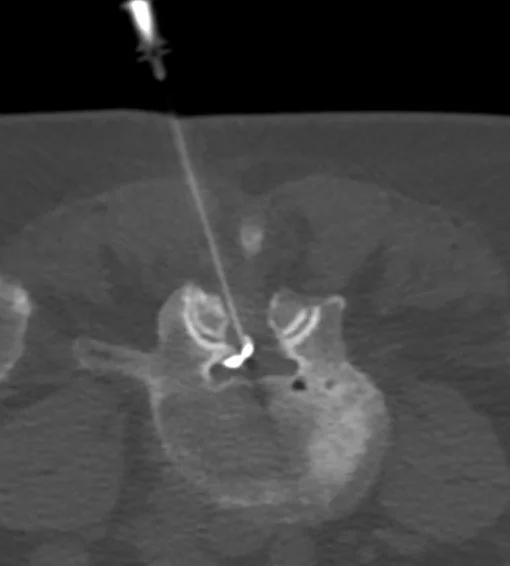

A CT-guided lumbar spine injection is a procedure used to deliver medication directly to the spine to treat pain, inflammation, or nerve irritation in the lower back. This injection can target different areas depending on the condition being treated, including:

Nerve Block: Used to target specific nerves, providing pain relief and helping to pinpoint the source of pain.

Epidural Injection: Aimed at reducing inflammation and pain in the epidural space, often for conditions like herniated discs or sciatica.

Facet Joint Injection: Focuses on the facet joints in the spine, often used to treat arthritis or joint-related pain in the lower back.

CT-Guided Lumbar Injections

Nerve Block/Perineural

Nerve blocks, also known as perineural injections, are used to target specific nerves that are causing pain, inflammation, or discomfort. This procedure is frequently used to treat conditions such as neuralgia or radiculopathy.

Epidural

An epidural injection is used to deliver medication directly into the epidural space of the spine. The procedure is commonly performed to treat chronic back pain caused by conditions such as herniated discs, spinal stenosis, or sciatica.

Facet Joint

Facet joint injections are used to treat pain originating from the facet joints in the spine, often caused by arthritis or degeneration. This can provides pain relief and reduces inflammation within the facet joint.